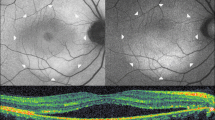

Figure 1 illustrates a representative case of macular NSD appearing as hyper-reflective dots on a diffuse hypo-reflective background in IR fundus images (Fig. 1a) and as granular hyper-autofluorescence on BAF images (Fig. 1b). The center of the AO-TFI montage shows contrast changes (Fig. 1c). The central blurred area corresponds to the area of serous detachment in the OCT sections (Fig. 1d and 1e), and the well-defined area with bright components surrounded by a darker edge (Fig. 1c, white arrow) corresponds to an irregular pigment epithelial detachment (PED) in OCT B-scans, also visible on the IR fundus as an ill-defined hyper-reflective area (Fig. 1a and 1e, white arrow). The presence of RPE cells in in the superior region of the blurred area on the AO-TFI montage (Fig. 1c, inset) correlates with an intact RPE layer in the OCT image (Fig. 1d).

Foveal serous detachment (Left eye, Female, 43 years). (a) Infrared fundus image with projection of the AO-TFI mosaic mask (Z5-Z6, Grade 1; Z1 to Z4, Grade 2). The colored lines indicate the locations of the OCT B-scan shown in panels d (blue line) and e (yellow line). (b) Blue-autofluorescence fundus image indicating the approximate hyper-reflective areas of NSD (orange circle) and the one imaged with Cellularis (white lines). (c–e) Correlation of the AO-TFI mosaic with OCT B-scans showing RPE layer under sub-retinal fluid (d) where RPE cells are imaged with AO-TFI (c, top blue line) and hyperreflective content (e, white arrow) where AO-TFI shows also hyper-reflective content in greater detail (c, white arrow) than IR fundus (a, white arrow). The complete “IR fundus—AO-TFI—OCT B-scan” correlation is available in the supplementary Movie S2.